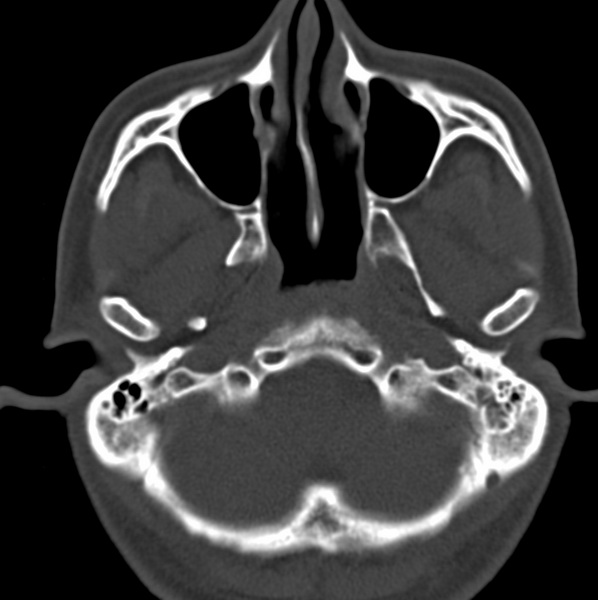

男、31、鼻咽部肿瘤放疗后请帮忙看看。

效果好,右侧破裂孔扩大,局部骨质缺损,为颅底骨质破坏。

1)鼻咽部肿瘤侵犯颅底放疗术后改变。2)左侧蝶窦炎。

咽后壁增厚,左侧咽鼓管隆突增大、咽鼓管咽口变浅,同侧咽旁间隙较窄。右侧颅底骨质破坏?为什么不在同一侧?

鼻咽部肿瘤侵犯颅底放疗术后改变.